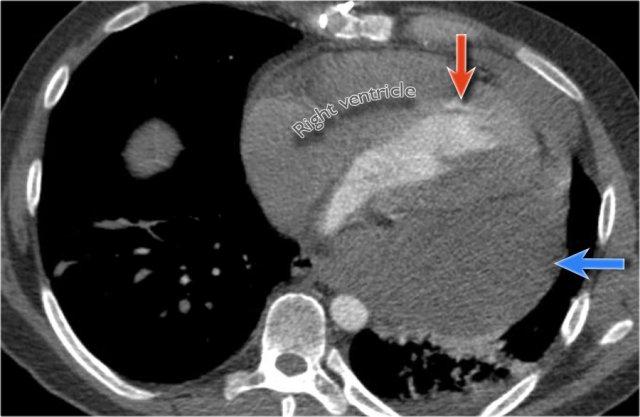

Tương quan trên CT

Giải thích cho hình ảnh khuyết tim được thể hiện rõ trên ảnh CT này.

Ở mức ngang tim dưới, thùy dưới phổi phải (mũi tên xanh dương) thường kéo dài ra phía trước nhiều hơn thùy dưới phổi trái (mũi tên đỏ), lý giải cho sự bất đối xứng của khuyết tim.